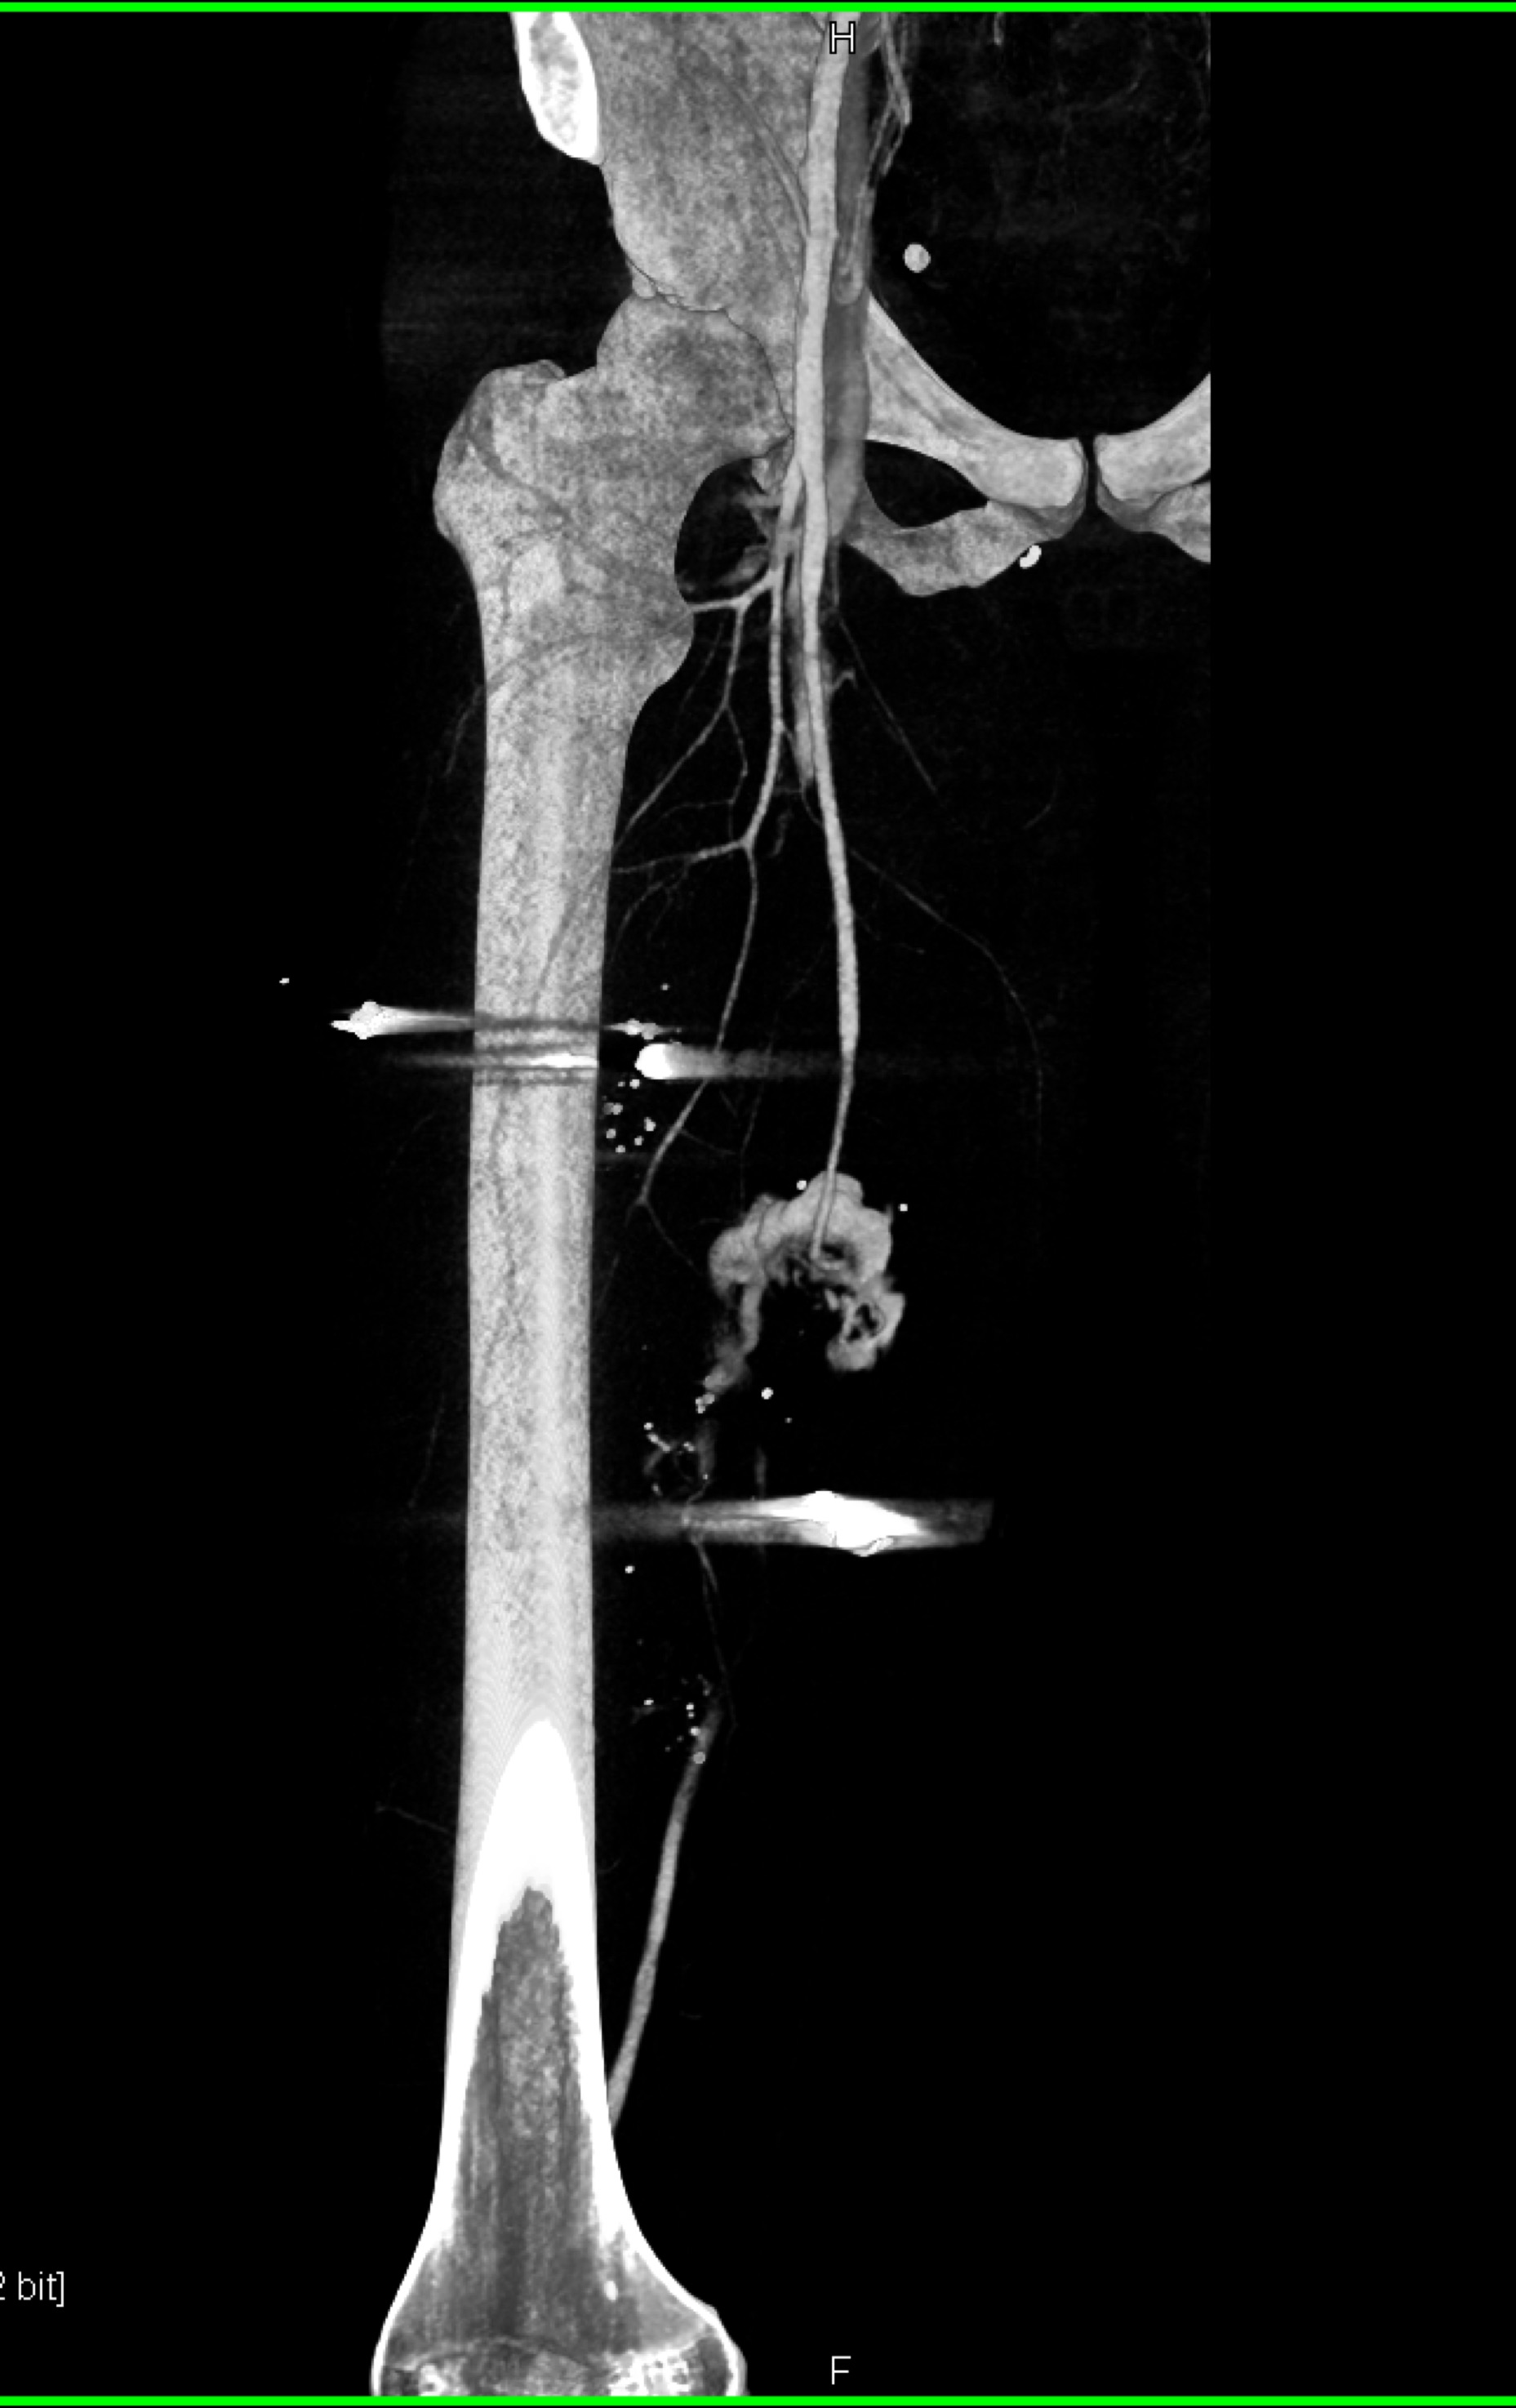

5) The most likely diagnosis in this case is?

femur fracture

GSW with active bleed from SFA

GSW without source of bleed

GSW with vessel spasm in SFA